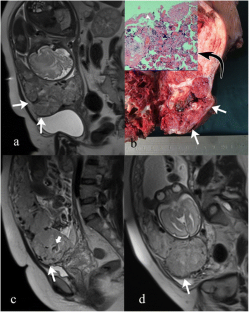

Fig. 2